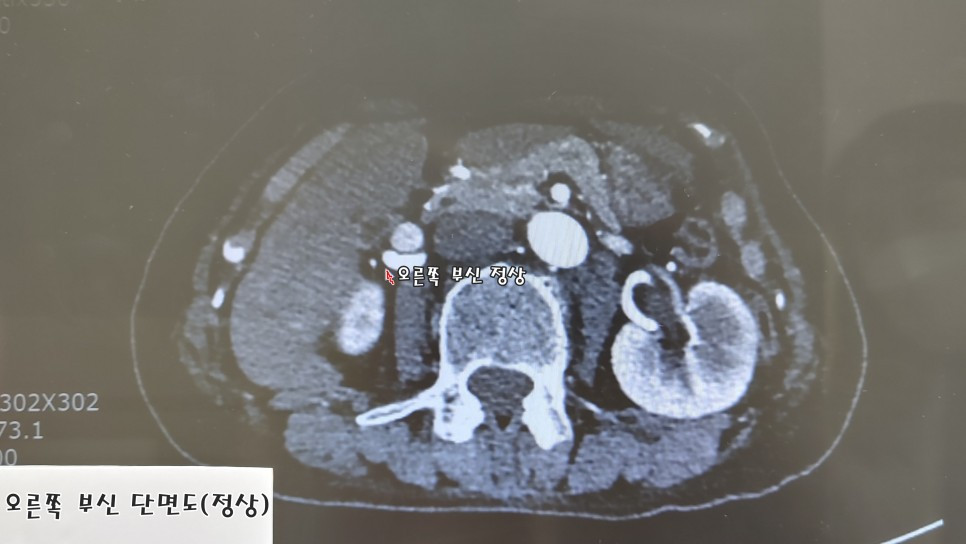

왼쪽 부신이 완전히 망가져 있었다.

오른쪽 부신 대비 50배까지 많은 알도스테론이 분비되고 있었다. 헉!

혹이 있는 부신이 정상이고, 혹이 없는 부신에서 알도스테론이 많이 나올 때,

다행히 나는 혹 있는 왼쪽 부신이 비정상이고, 오른쪽 부신은 정상임이 정맥 채혈로 확인됐다.